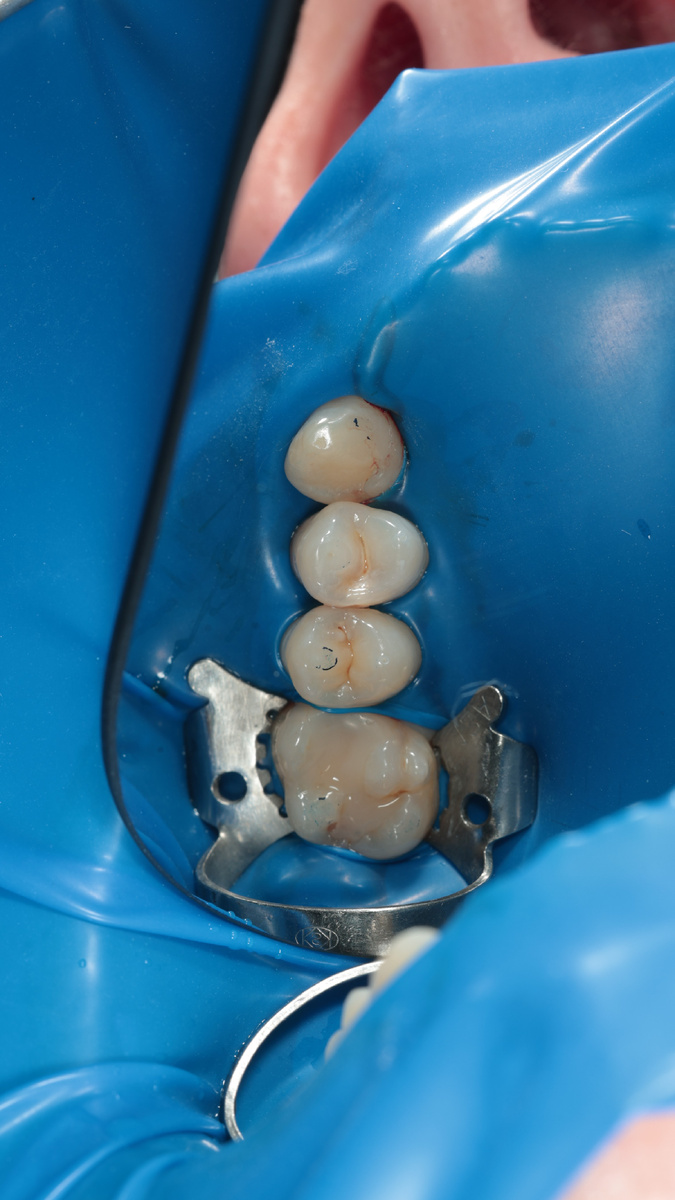

На сегодня у нас зуб 2.4, хотя на 2.3 тоже виднеется кариес, как только убрали стенку

Вычищено все до скрипа в зубе 2.4

Зуб 2.4 готов